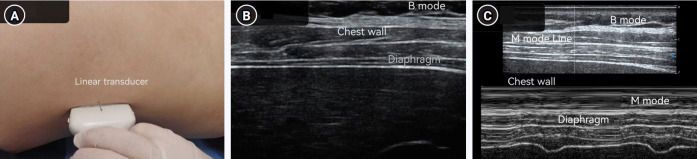

Methods: This study included 246 patients undergoing the spontaneous breathing trial. Diaphragmatic function was evaluated by ultrasound, including the diaphragm thickness at the end of calm breathing (thickness of the diaphragm at functional residual capacity [TdiFRC]) and the maximum diaphragm thickness at the end of inspiration (thickness of the diaphragm at full vital capacity [TdiFVC]); TF=(TdiFVC-TdiFRC)/TdiFRC×100%. DM, the oxygenation index (the ratio of the partial pressure of arterial oxygen to the fraction of inspired oxygen), and the rapid shallow breathing index (RSBI) were measured.